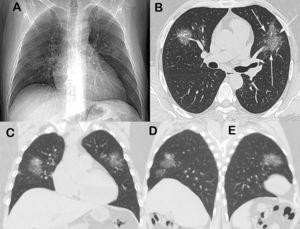

tudo koronavirus

Koronavírus okozta tüdőgyulladás röntgenfelvétele (a fehér rész az érintett)

Forrás: https://www.journalpulmonology.org/